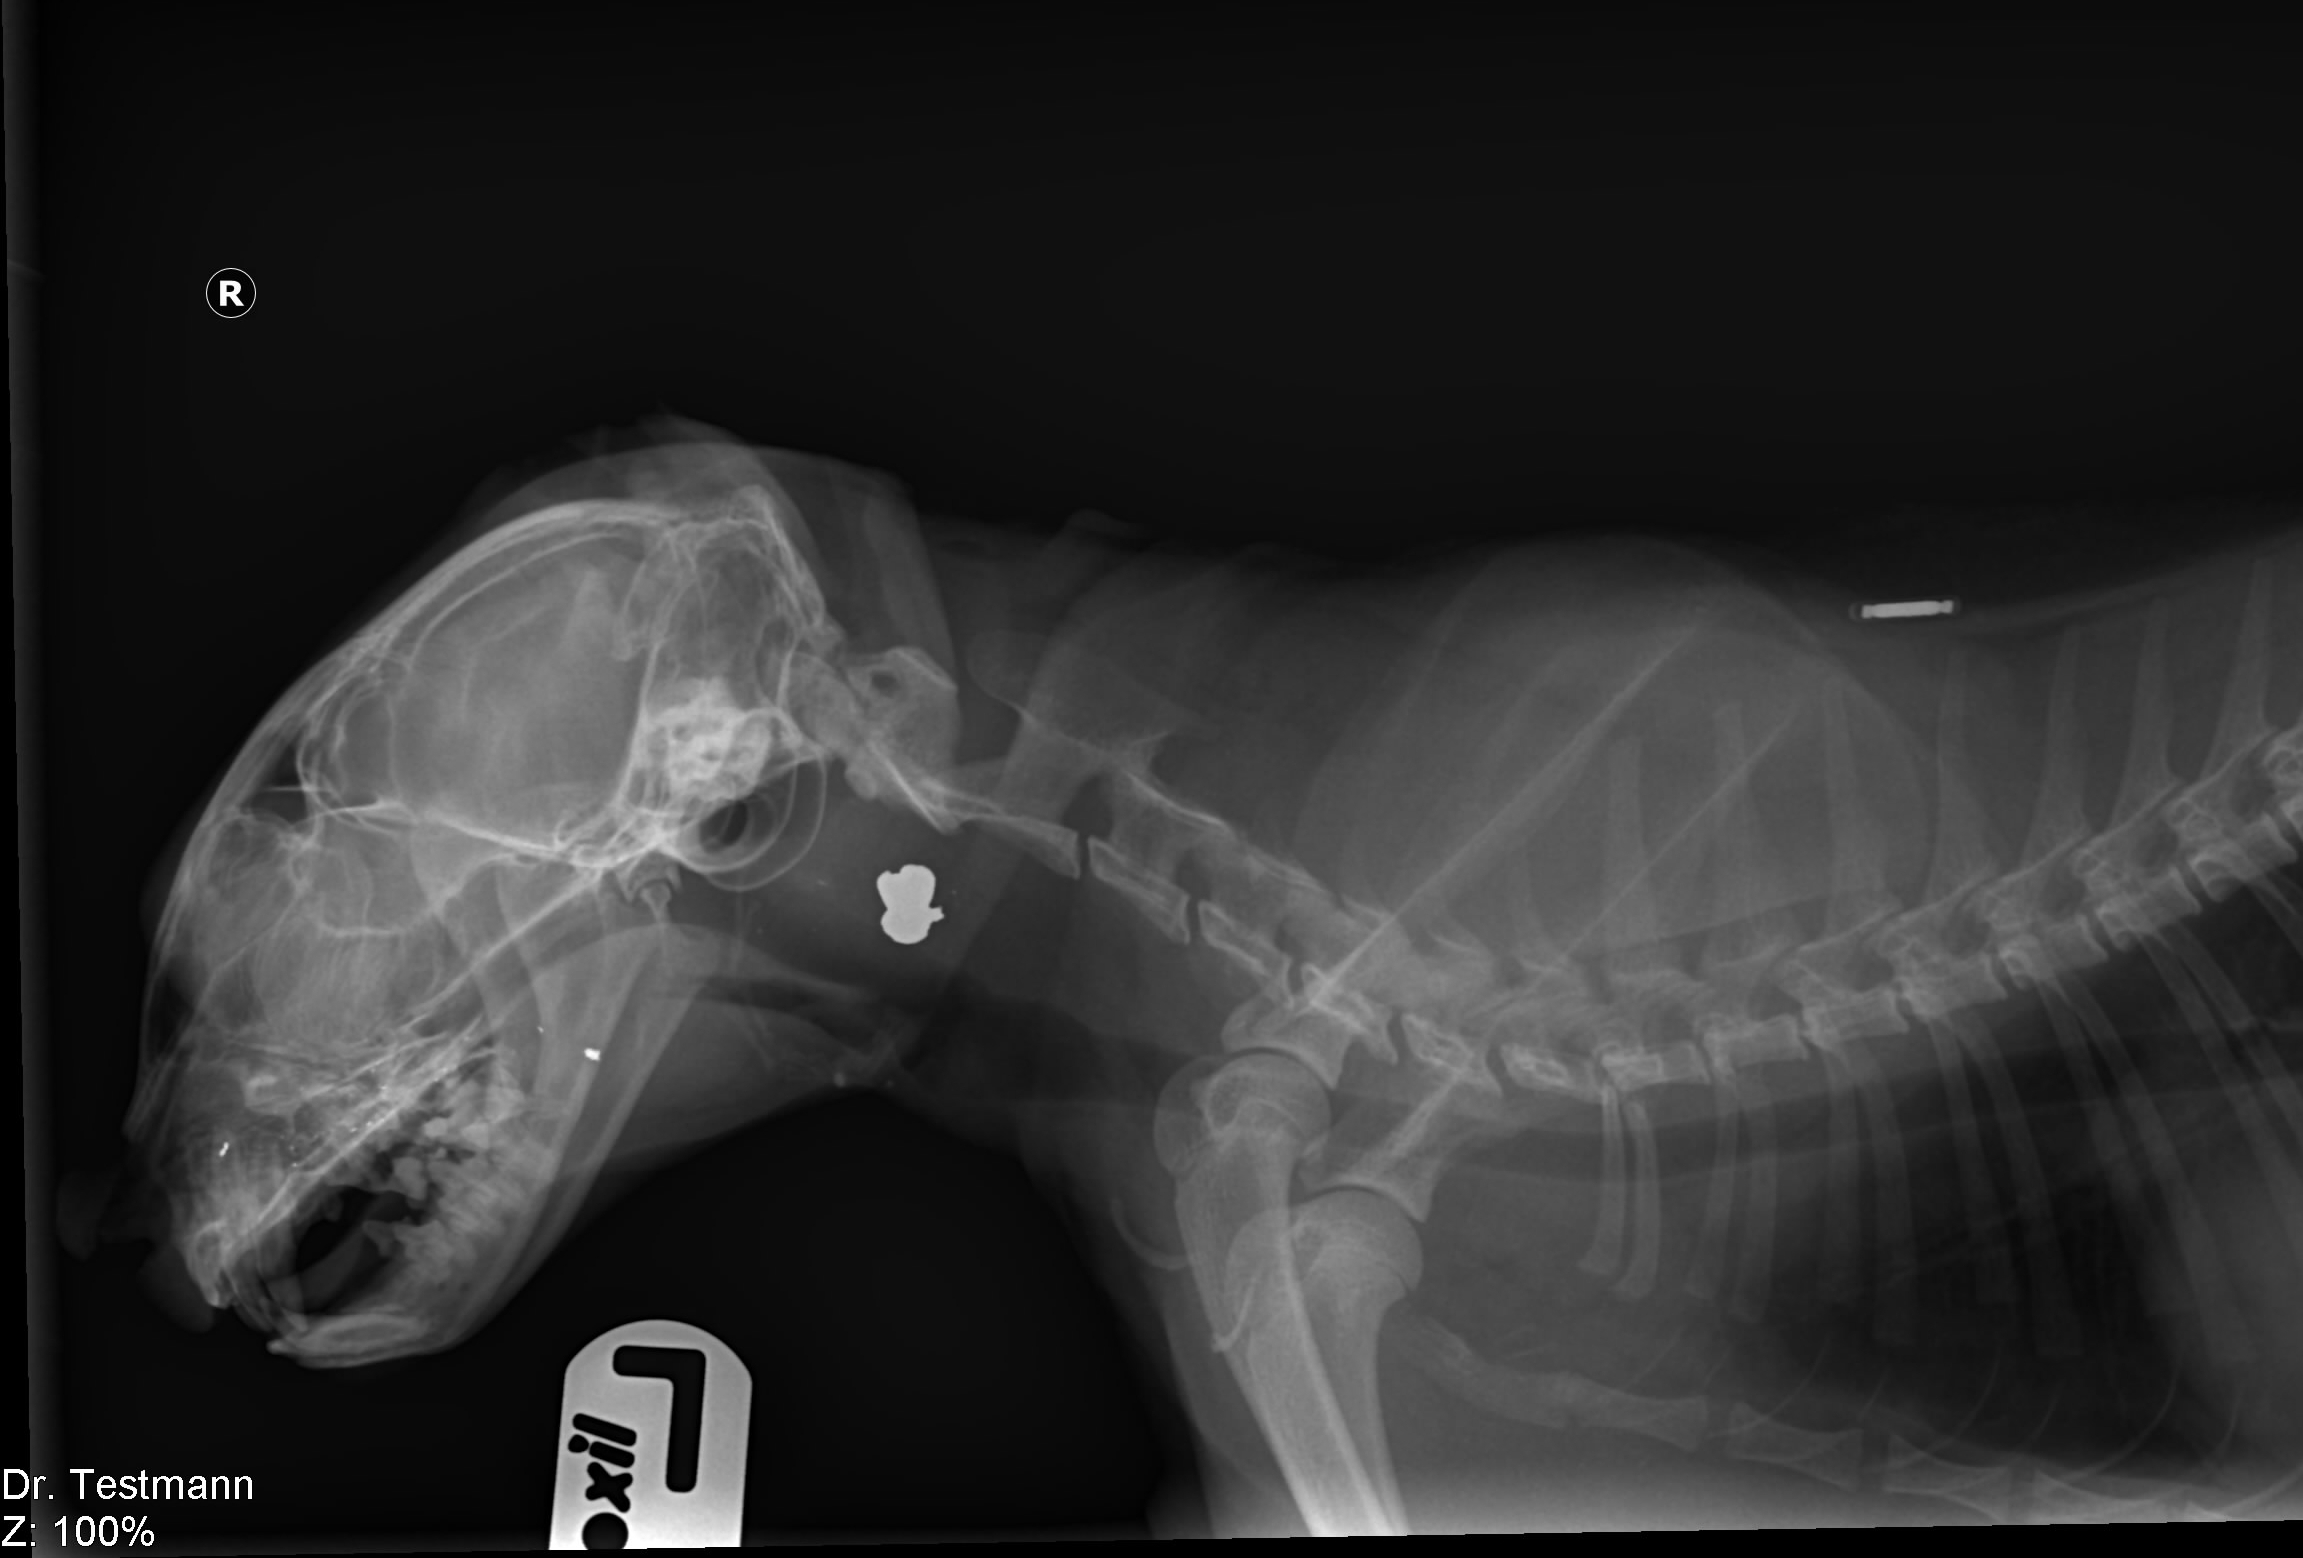

Особую проблему представляет собой хирургия пищевода грудного отдела. Операция проходит в грудной полости в условиях искусственной вентиляции лёгких. Для проведения подобного оперативного вмешательства необходимо чётко знать местоположение инородного тела в пищеводе, так как разное положение определяет место доступа в грудную полость. Для этого необходимо провести эзофагогастроскопию животному (фото 4,5,6,7).

Фото 4а, 4б, 4в: Кость в пищеводе грудной части у йоркширского терьера

На фото 5а, 5б, 5в: Кость в пищеводе грудной части у грифона

- Рентгенография – позволяет рассмотреть петли тонкого кишечника, располагающиеся в центральной зоне брюшной полости в двух проекциях – вентродорсальная и боковая. Аномальное расширение исследуемого материала сигнализирует о растяжении от постороннего предмета или от иных причин. На снимке можно обнаружить металлические вещи, кости, камни, стекло. Впрочем, не всегда инородные тела видны с помощью рентгенографии. Так, сложно обнаружить на снимке нитки, резиновые изделия, полиэтилен или тряпку. В этом случае применяют контрастную рентгенографию или другие способы исследования.

Ваш ветеринар может порекомендовать рентген брюшной полости, чтобы лучше понять, что происходит в брюшной полости. Они будут искать инородное тело, а также обнаруживать изменения в газовой структуре кишечника (что указывает на закупорку).

Рентгенограммы (рентгеновские снимки) были сделаны для оценки его живота.

Твердый объект располагался в кишечнике в каудальном левом квадранте брюшной полости.Поскольку он перекрывал толстую кишку, не сразу было очевидно, находится ли объект в тонком или в толстом кишечнике. Мы провели ультразвуковое исследование его брюшной полости и обнаружили объект в тонкой кишке, на полпути между желудком и толстой кишкой.

При подозрении на инородное тело рентгенограммы (рентгеновские снимки) часто являются первым рекомендуемым тестом. В случае подозрения на инородное тело пищевода, скорее всего, будет рекомендована рентгенография грудной клетки. Если есть подозрение на инородное тело в желудке или тонком кишечнике, будет рекомендована рентгенограмма брюшной полости. УЗИ брюшной полости часто используется, чтобы определить, какая часть кишечного тракта задействована, чтобы спланировать терапию.